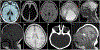

Purpose: Congenital microcephaly (CM) is an important birth defect with long term neurological sequelae. We aimed to perform detailed phenotypic and genomic analysis of patients with Mendelian forms of CM.

Conclusion: Our study refines the phenotype of CM, expands its genetics heterogeneity, and informs the workup of children born with this developmental brain defect.